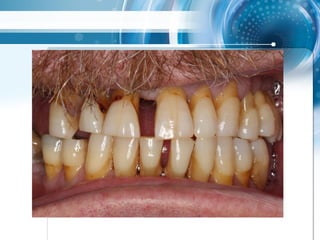

• Multiple Änderungen von Modellsituation nach CT

scan, Extraktionen und Wurzelfüllungen realisiert,

4 geplante Extraktionen

Triple scan Technik

Triple scan Technik •Multiple Änderungen von Modellsituation nach CT scan, Extraktionen und Wurzelfüllungen realisiert, 4 geplante Extraktionen

• 54.

• 55.

• 56.

• 57.